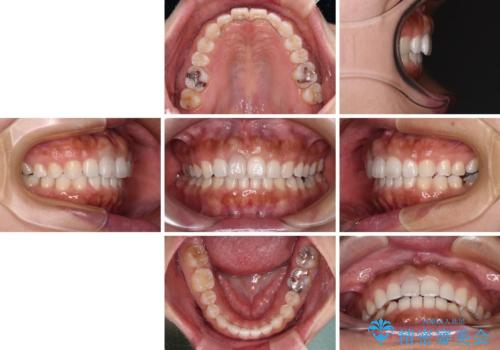

隙間の空いた前歯を閉じたい インビザライン矯正

- 前歯の隙間を気にして来院された患者様です。

隙間、捻転ともに軽微でありましたが、下顎前歯の突き上げにより隙間ができていたため、インビザラインを用いて咬み合わせを改善しながら前歯の歯列を整えていくこととしました。

当初は1年程度で終えられると思いましたが、治療途中から装着時間が短くなったり、来院間隔が長期になったりとし、結果として4年半以上の治療期間となりました。

治療途中に上顎前歯は失活してしまいましたが、変色が顕著ではないため、経過を見ていくこととなりました。